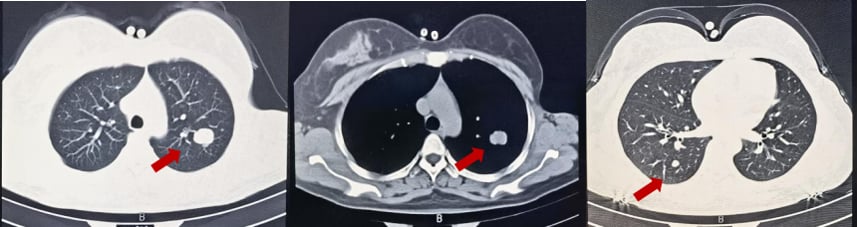

2025年2月,患者再次出现疾病进展,头颅MR显示左侧额顶叶异常强化软组织肿物,伴周围脑组织水肿,考虑脑转移。胸腹部CT显示肝脏病灶增大。

面对脑转移的再次出现,MDT团队决定启用新一代ADC药物——T-DXd(德曲妥珠单抗)。德曲妥珠单抗是目前HER2阳性乳腺癌治疗领域的一颗“新星”,它具有更高的药物抗体比(DAR),即每个抗体携带更多的化疗药物分子,同时具有“旁观者效应”,可以杀死周围未表达HER2的癌细胞。这使得它在治疗HER2低表达和脑转移方面展现出卓越的疗效。

患者接受了11周期的德曲妥珠单抗治疗。仅仅2周期后,患者右下肢无力症状明显好转;4周期后,右下肢肌力恢复,ECOG评分达到0分(意味着完全正常活动)。治疗过程中,骨髓抑制I-II度,胃肠道反应I度,未见间质性肺炎等严重副作用。影像学复查显示,疗效评价为部分缓解(PR)。这再次证明了创新药物在多线治疗失败后,仍能为患者带来显著的生存获益和生活质量改善。